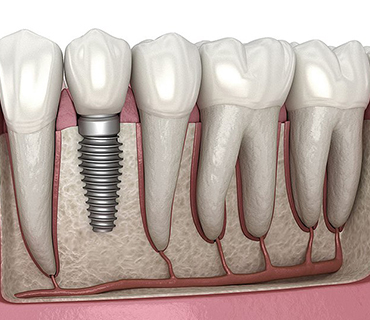

Dental Implants

Dental implants are most popular in replacing your missing teeth/tooth

Dental implants is the surgical placement of titanium post into the jawbone, then placement of crown done

Why Dental Implants?

- Natural looking & natural feeling of replacement for missing teeth

- Don't slip or click when you talk, laugh or eat

- Keeps your jawbone healthy & facial structure intact